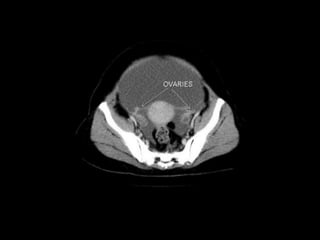

CT cross sectional

anatomy.